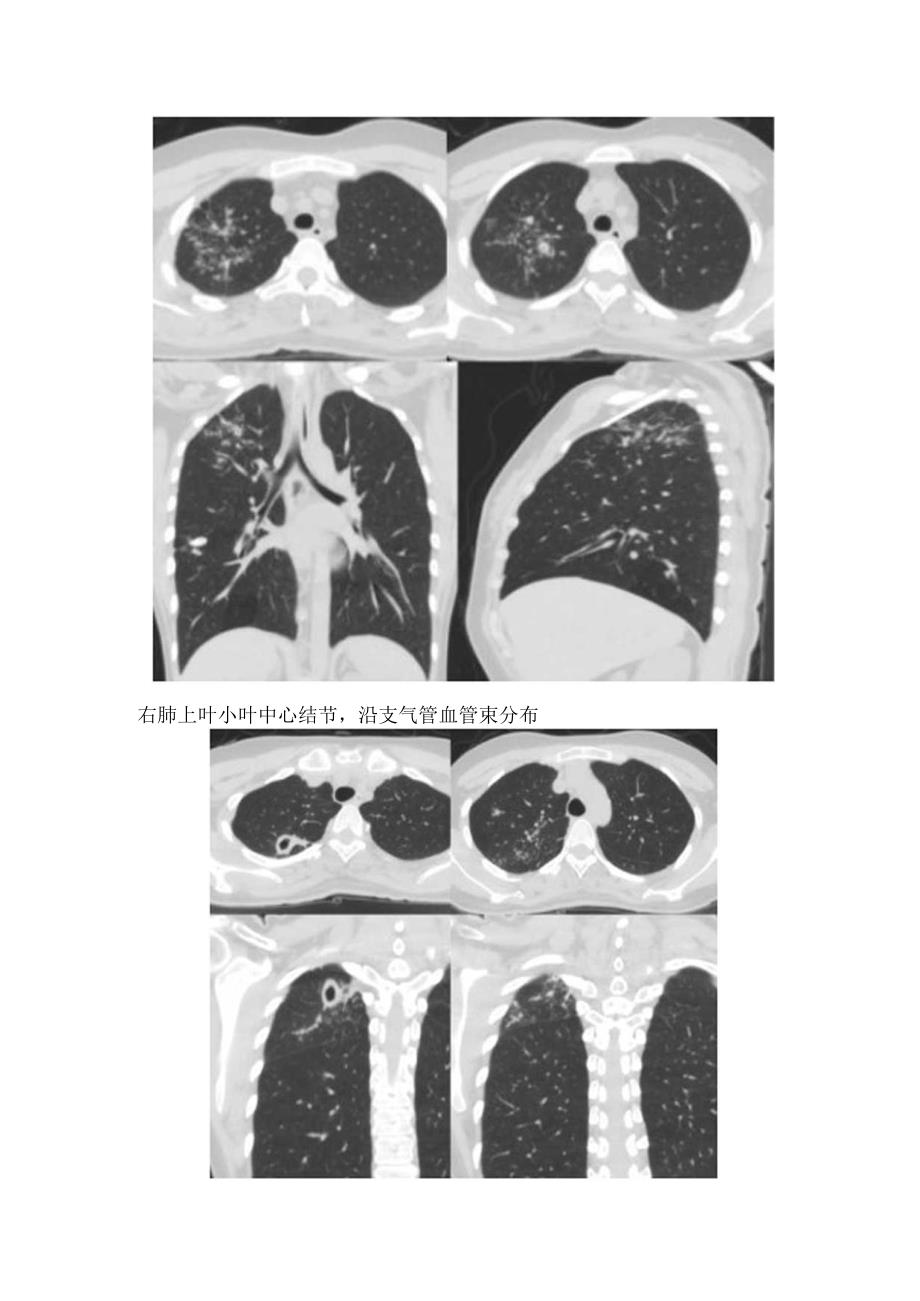

2、壁空洞右肺上叶小叶中心结节,沿支气管血管束分布右肺上叶小叶中心结节,沿支气管血管束分布右肺上叶、左肺多发结节及实变影,沿支气管血管束分布,同时左肺上叶见薄壁空洞右肺下叶背段多发小结节,沿支气管血管束呈树芽状分布左肺上叶尖后段簇状分布小结节右肺下叶簇状分布多发小结节特征四:伴有支气管播散气管及左主支气管可见沿着支气管壁播散,左肺上叶厚壁空洞形成(八),抗结核治疗后空洞消失特征五:粟粒状结节双肺粟粒状结节(八)特征六:肺门和纵膈淋巴结增大,直径大于2cm的淋巴结边缘强化双肺粟粒状结节(八),纵隔肿大淋巴结边缘强化(b)气管隆突卜淋巴结伴坏死,边缘强化,突入到右主支气管:右肺下叶实变及胸腔积液右肺上叶不规则活动性肺结核,纵隔淋巴结肿大及边缘强化,PET-CT为高代谢左肺上叶空洞影和实变影;纵隔淋巴结肿大,边缘强化特征七:伴有胸膜肥厚及胸腔枳液或支气管胸膜楼双肺簇状小结节,沿支气管周围分布:左侧胸膜肥厚及强化,伴左侧胸腔积液:纵隔淋巴结肿大特征八:反晕征,是一个局灶性圆形弱毛玻璃区域,由几乎完整的实性环包绕。CT表现为一局灶性圆形磨玻璃区,围绕完整的实变环双肺出现厚壁反晕征以结节堆积为主的反晕征,可有小结节、树芽征并存以结节堆枳为主的反晕征,可有小结节、树芽征并存